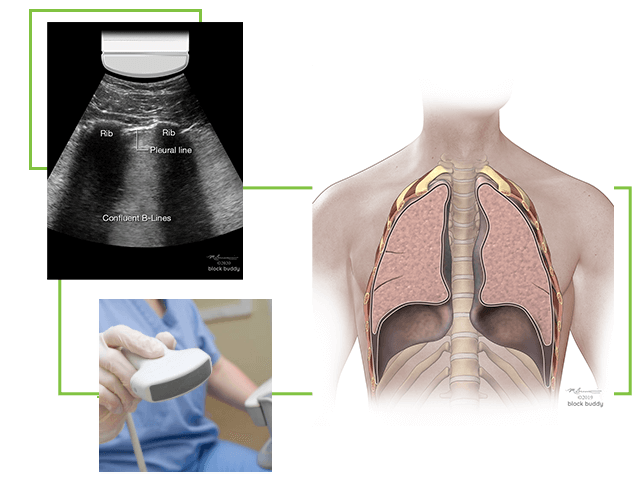

B-Lines

- Hyperechoic, vertical reverberation artifacts.

- Extend from the pleural line to the bottom of the screen.

- Obliterate A-lines.

- Move synchronously with lung sliding.

- Results from interlobular septal thickening (fluid) surrounded by air filled alveoli.

- This produces a significant acoustic impedance gradient, resulting in the reverberation artifacts.

- Most commonly seen in pulmonary edema (cardiogenic and non-cardiogenic).

- Also seen with interstitial pneumonia, acute respiratory distress syndrome (ARDS), pulmonary fibrosis, pulmonary contusion, atelectasis and malignancy.

- 2 or less B-lines between 2 ribs in any zone are a normal finding.

- 3 or more B-lines between ribs in any zone are pathologic.

- The presence of B-lines can be used to identify interstitial syndrome, but cannot distinguish between pulmonary edema, ARDS, or fibrosis.

- B-lines with lung sliding are indicative of pulmonary edema.

- B-lines without lung sliding, may indicate ARDS or pneumonia.

Moderate to Severe COVID-19

- Pleural line is thickened, irregular and interrupted

- Multiple or confluent B-lines

Pulmonary Edema

- Results from an increase of fluid in the lung interstitium.

- Lung sliding is present.

- 3 or more B-lines in at least 2 zones confirm the presence of pulmonary edema.

- Pulmonary edema is the most common cause of B-lines.

- As the severity of the edema progresses, multiple diffuse B-lines are produced.

- A hyperechoic confluent pattern (white out) between the ribs may occur as the B-lines fuse together.